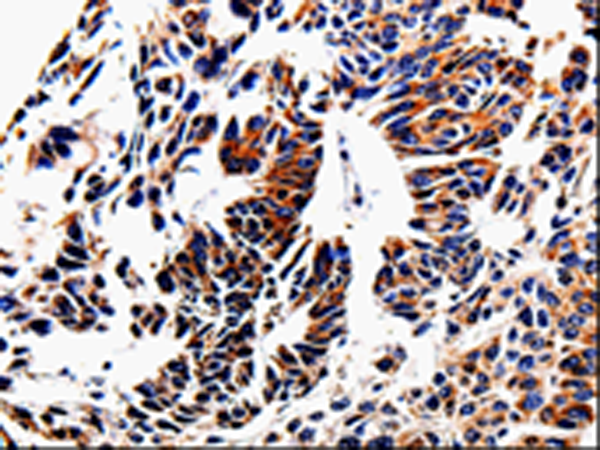

分类: 科研抗体货号: P06944别名: FN; CIG; FNZ; MSF; ED-B; FINC; GFND; LETS; GFND2应用: IHC反应种属: Human, Mouse, Rat